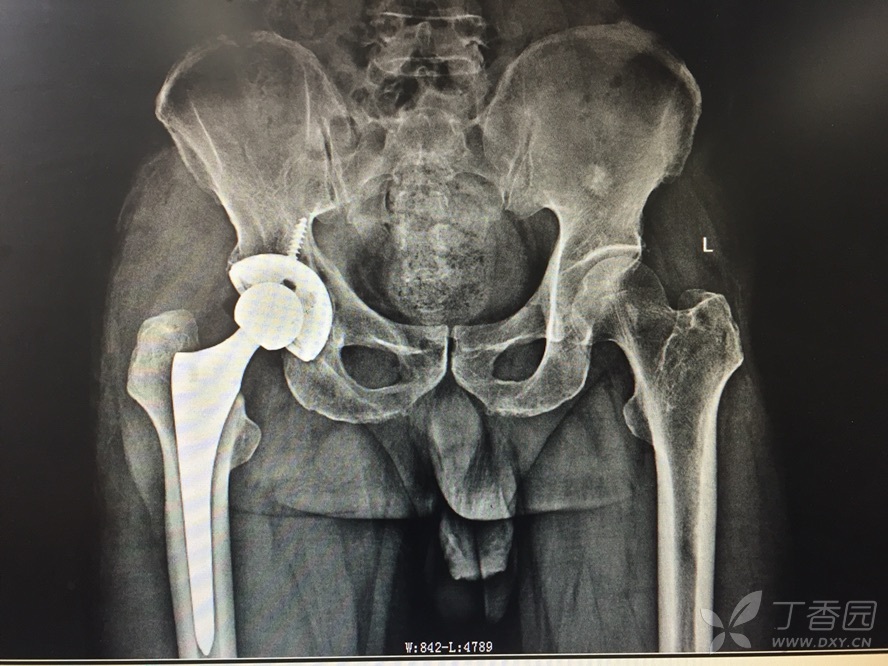

胡孔足大夫成功完成一例严重髋臼骨折的全髋置换术

图片尺寸600x450